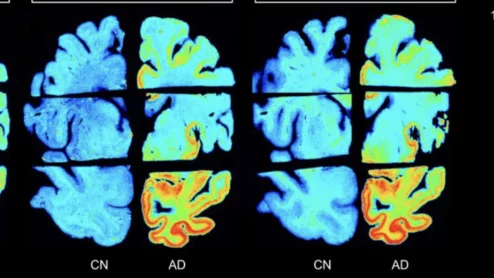

New radiotracers outperform FDA-approved agent for detection of tau tangles.

If approved, the two agents could offer providers greater insight into the process of patients’ neurodegeneration.